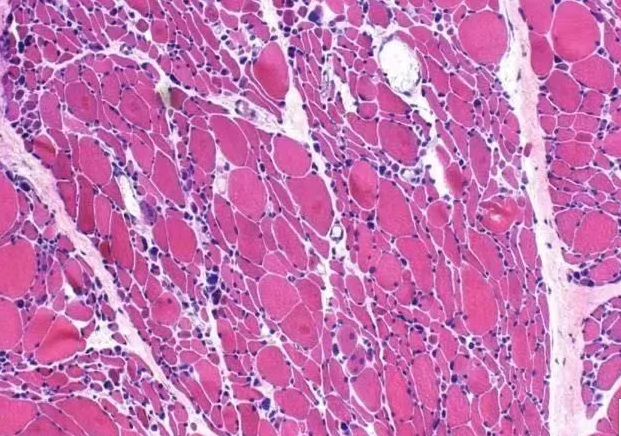

人体大约有600多块骨骼肌,每块肌肉由许多肌束组成,每条肌束再由肌纤维聚集而成。当肌纤维发生结构或功能改变,或出现能量代谢障碍,就会产生各种肌肉疾病。

当肌纤维病变后会出现体积变小或数目减少,达到一定程度就会出现肉眼可见的肌萎缩。但有些肌肉疾病会出现肌肉肥大,主要是由于肌肉组织受到病变刺激代偿增生或局部肌肉组织中的脂肪组织与结缔组织增生所致。

当出现上述症状时,请注意有肌肉疾病可能。肌肉疾病中,遗传性疾病占有一定的比例,所以当有亲属也有类似表现时,需格外警惕。我院神经内科,具备肌肉疾病诊治的专业能力。肌电图室可完成肌肉相关疾病的定位诊断,影像学包括肌肉核磁可协助评估受累肌群范围及病变程度,肌肉活检及病理检查可进一步明确病因。同时可外送基因检测协助遗传性肌肉疾病诊断。